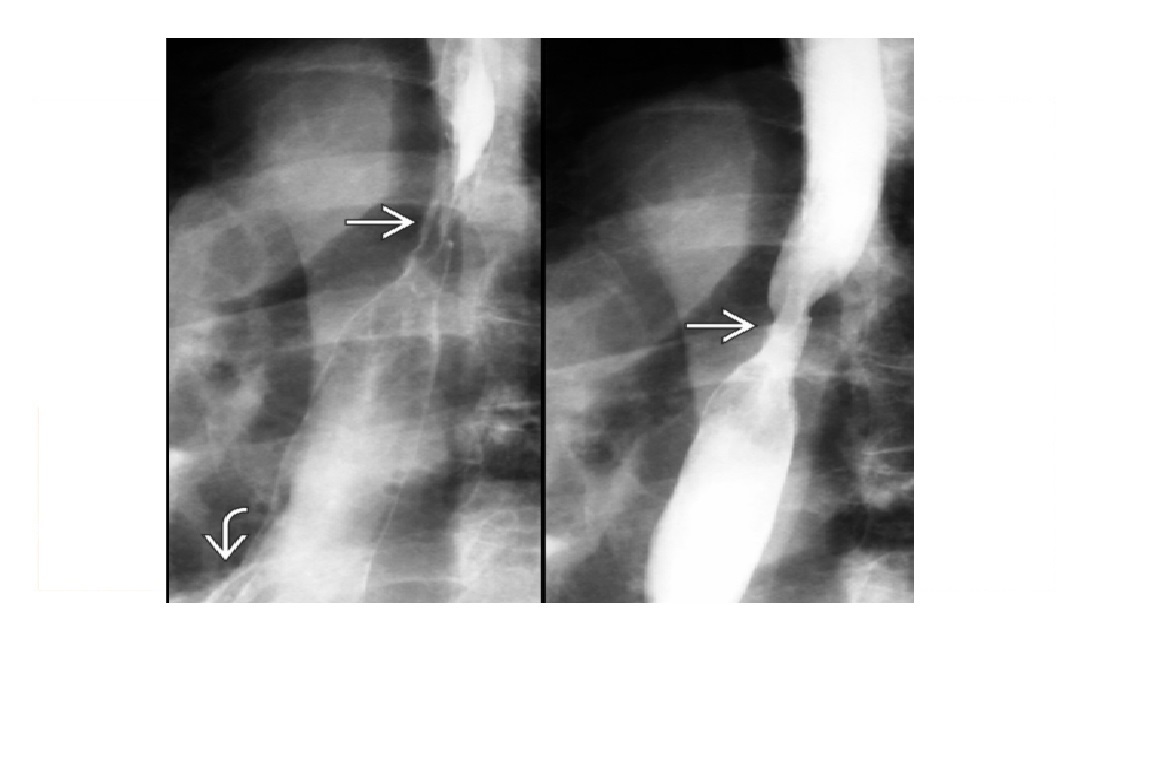

oesophageal scleroderma

-affects the Lower 2/3 (smooth muscle) with atony and peristalsis that begin caudally and moves cranially.

-Moderate dilatation of esophagus with fusiform stricture at lower end

Nb upper 1/3 to above aortic arch is normal (striated muscle)

Achalsia

- Grossly dilated whole oesophagus with smooth, beak-like tapering at lower end

Reflux Esophagitis (With Stricture)

-Longer tapered distal stricture

-Less luminal dilation

-Distinguished from scleroderma by normal peristalsis

Esophageal Carcinoma

-Abrupt proximal borders of strictured segment (rat tail appearance)

-Mucosal irregularity, shouldering, mass effect